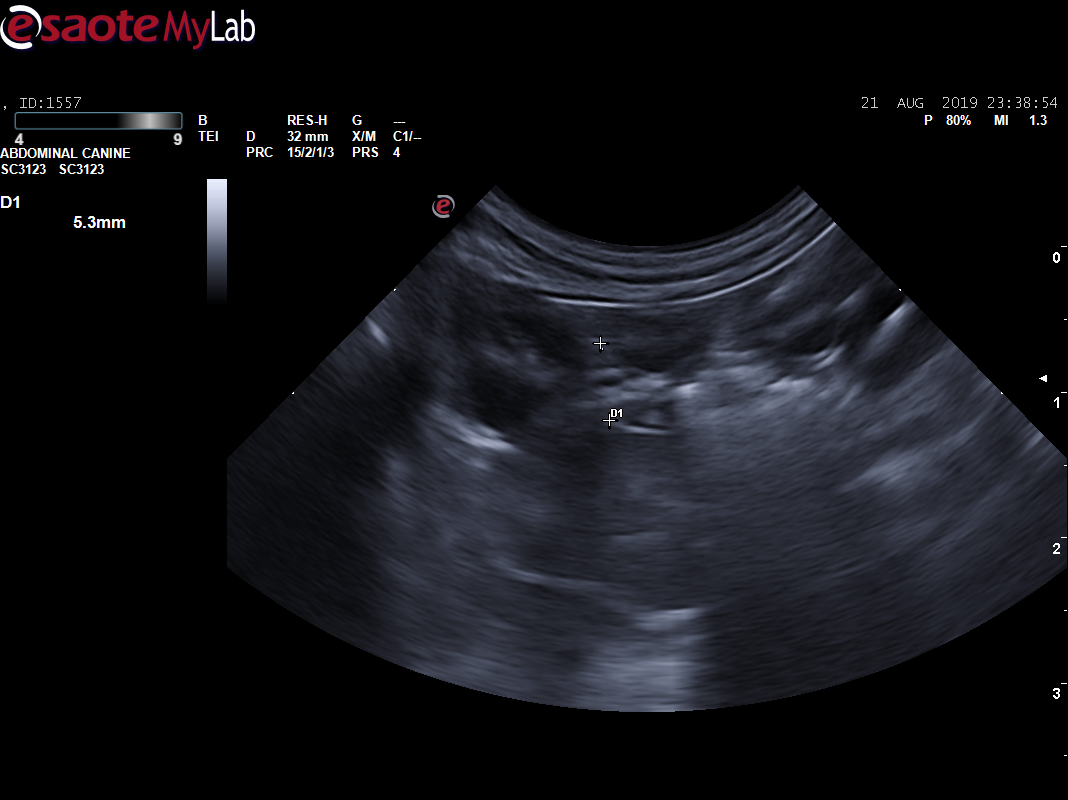

主人叙述2年前体检时,B超检查查出腹腔肿物(直径约6.1CM,场回声团块 ),主人当时选择保守治疗。每天吃完就吐,频繁的呕吐(3-4),导致梦龙体重急剧下降,主人十分担心。到我院初步诊断发现腹部触诊敏感,前腹部大肿物明显,为了准确评估梦龙的情况,医生对梦龙做了X光、生化和B超检查,进一步了解梦龙的身体情况。

B超显示:脾脏弥散性低回声(鉴别肥大细胞瘤、淋巴瘤、充血等),腹部肿物(鉴别淋巴瘤、肥大细胞瘤、肉瘤),肾脏(鉴别肾小球肾炎、慢性肾炎)。